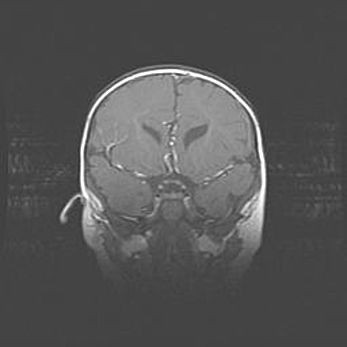

Открытая гидроцефалия.

Возраст: 9 месяцев 12 дней

Вес: 6800 г

Пол: мужской

Окружность головы: 41,5 см

Срок гестации: 28 недель

Гидроцефалия головного мозга у новорожденных имеет характерный признак: опережающий рост окружности головы приводит к визуально хорошо определяемой гидроцефальной форме сильно увеличенного в объёме черепа. Детские неврологи определяют следующие симптомы гидроцефалии у грудничков: выбухающий напряжённый родничок, частое запрокидывание головы, смещение глазных яблок к низу.